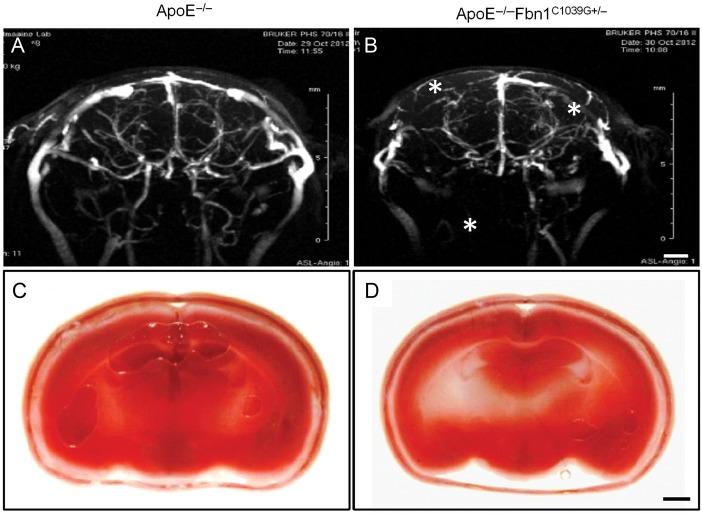

Female ApoE(-/-)Fbn1(C1039G+/-) and ApoE(-/-) mice were fed a WD for up to 35 weeks. Compared to ApoE(-/-) mice, plaques of ApoE(-/-)Fbn1(C1039G+/-) mice showed a threefold increase in necrotic core size, augmented T-cell infiltration, a decreased collagen I content (70 ± 10%), extensive neovascularization, intraplaque haemorrhage, and a significant increase in matrix metalloproteinase-2, -9, -12, and -13 expression or activity. Plaque rupture was observed in 70% of ascending aortas and in 50% of brachiocephalic arteries of ApoE(-/-)Fbn1(C1039G+/-) mice. In ApoE(-/-) mice, plaque rupture was not seen in ascending aortas and only in 10% of brachiocephalic arteries. Seventy percent of ApoE(-/-)Fbn1(C1039G+/-) mice died suddenly, whereas all ApoE(-/-) mice survived. ApoE(-/-)Fbn1(C1039G+/-) mice showed coronary plaques and myocardial infarction (75% of mice). Furthermore, they displayed head tilt, disorientation, and motor disturbances (66% of cases), disturbed cerebral blood flow (73% of cases; MR angiograms) and brain hypoxia (64% of cases), indicative of stroke.

雌性ApoE(-/-)Fbn1(C1039G+/-)和ApoE(-/-)小鼠喂食WD长达35周。与ApoE(-/-)小鼠相比,ApoE(-/-)Fbn1(C1039G+/-)小鼠的斑块坏死核心大小增加了两倍,T细胞浸润增强,I型胶原蛋白含量降低(70±10%),广泛的新生血管形成,斑块内出血,基质金属蛋白酶-2、-9、-12和-13的表达或活性显著增加。在ApoE(-/-)Fbn1(C1039G+/-)小鼠的70%升主动脉和50%头臂动脉中观察到斑块破裂。在ApoE(-/-)小鼠中,升主动脉未观察到斑块破裂,仅在10%的头臂动脉中观察到。70%的ApoE(-/-)Fbn1(C1039G+/-)小鼠突然死亡,而所有ApoE(-/-)小鼠存活。ApoE(-/-)Fbn1(C1039G+/-)小鼠出现冠状动脉斑块和心肌梗死(75%的小鼠)。此外,它们表现出头部倾斜、定向障碍和运动障碍(66%的病例),脑血流紊乱(73%的病例;磁共振血管造影)和脑缺氧(64%的病例),提示中风。